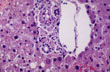

Fig 10 - INTERLOBULAR BILE DUCTS

These ducts, less than 1/10th of a mm in diam., are located in the portal field near the portal artery. They are lined by cuboidal epithelium and are surrounded by a basement membrane and loose collagen and elastic fibers. These components change in various types of bile duct injuries.